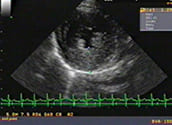

- 超音波検査

拡大した左心房と逆流シグナル(僧帽弁閉鎖不全症)